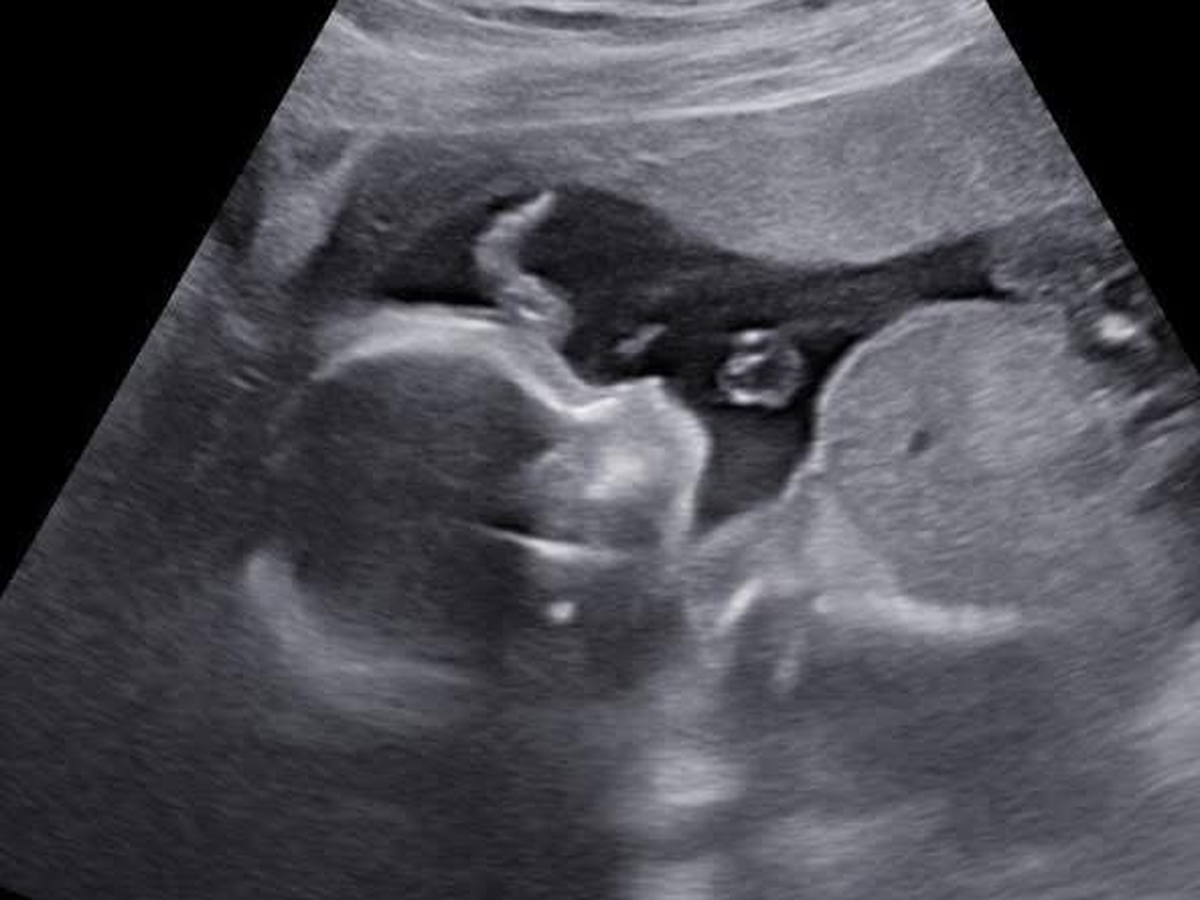

My name is Tyra and I am creating this gofund me for my sister and brother in law. Trista (my sister) has been off of work since September due to complications and sickness with her pregnancy. She was admitted to Good Sam’s with severely high blood pressure after speaking to her doctor she got transferred to St. Mary’s hospital in St. Louis Missouri. After multiple test, it has came back that she has severe preeclampsia. Trista is only 23 weeks pregnant as of 10/10. She will stay in St.Marys until she delivers her sweet baby boy. Doctors have talked as if she won’t go full term. They told her the farthest the she will go is 34 weeks and by 34 weeks they will deliver the baby if she makes it that far. Anything will help as her fiancé and family travels to her. Whether it’s for food, gas, hotel stays, anything would truly help! Please keep my sister, my nephew and brother in law in your prayers!